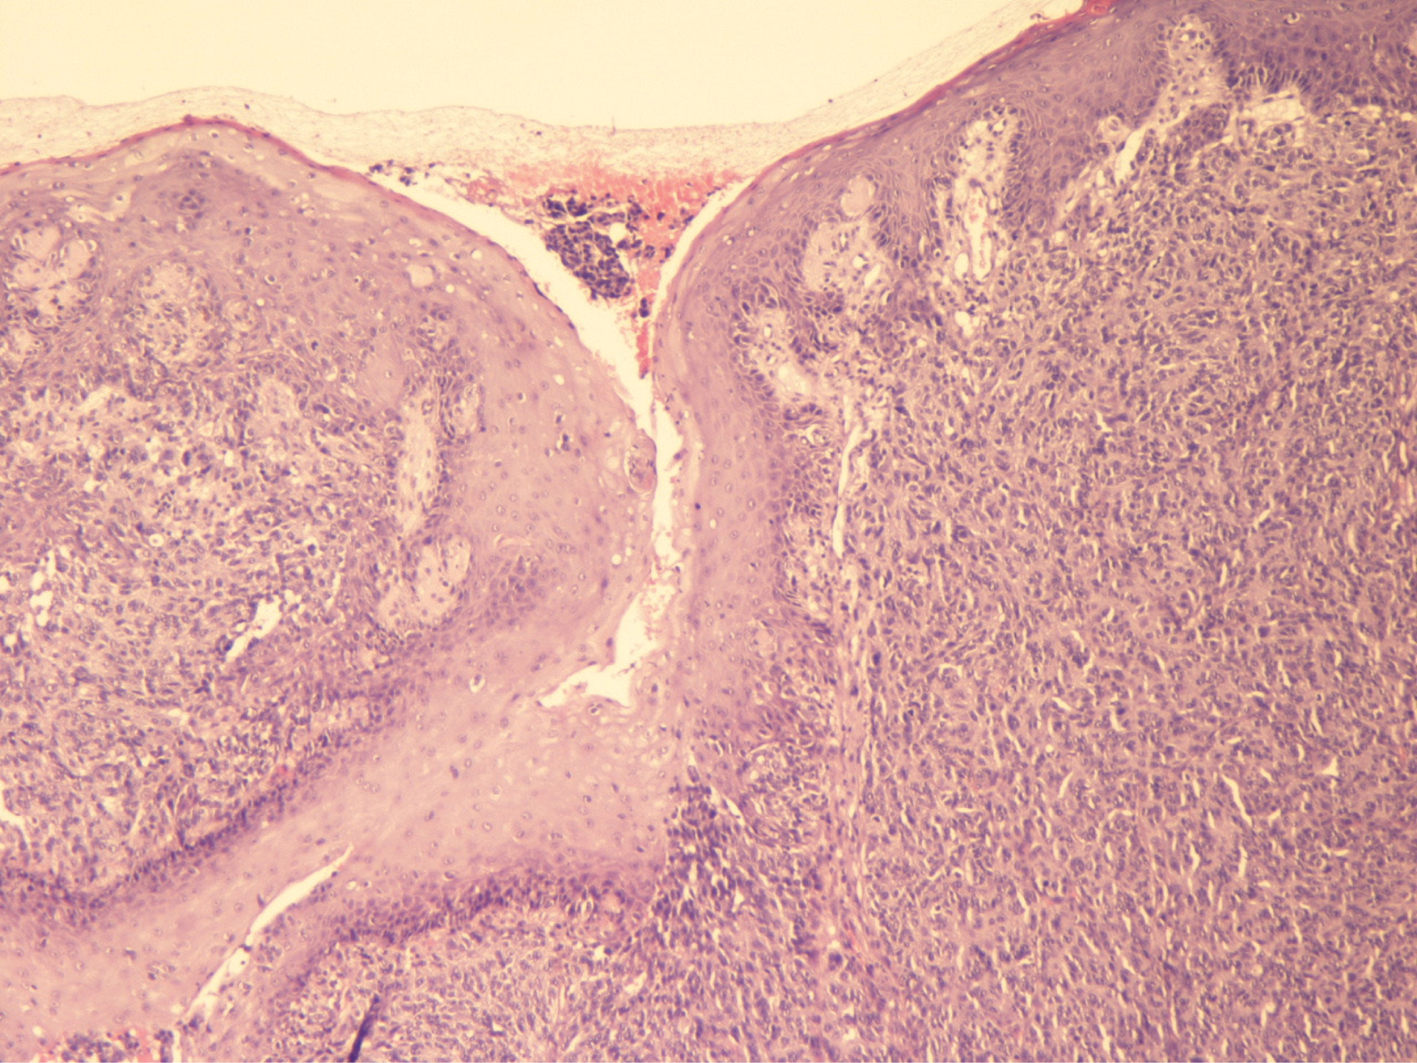

NPM is often amelanotic, resembling a benign polypoid lesion. Therefore, histology plays a pivotal role for a correct diagnosis (Figures 1 and 2). However, NPM can be also confused with other tumors, such as undifferentiated small blue cell tumors of the sinonasal tract, including olfactory neuroblastoma, sinonasal undifferentiated neuroendocrine carcinoma, Ewing’s sarcoma, peripheral neuroectodermal tumor (PNET), and rhabdomyosarcoma. Other differential diagnoses include squamous cell carcinoma and non-Hodgkin lymphoma. Accordingly, immunohistochemistry also plays an important role in the diagnosis. Human melanoma black (HMB)-45 reaches the 100% specificity for melanoma, while Melan-A is slightly less specific (2930). According to Morris et al., PNL-2 is a highly sensitive marker for mucosal melanoma, superior to Melan-A and microphthalmia-associated transcription factor (MITF) and comparable with HMB-45 (29). Therefore, PNL-2 can be evaluated as an important adjunctive marker in the immunohistochemical evaluation of PMMs (26, 27). Furthermore, it is often difficult to distinguish a metastasis from a primary neoplasm. However, a de novo primary NPM is much more likely than a metastasis, although at the time of diagnosis, up to 50% of patients with primary NPM develop distant metastases to the brain, liver, and lungs (3). Therefore, after a diagnosis of an NPM, it is important to perform a general dermatological consultation, followed by a trachea-laryngoscopy, gastro-duodenoscopy, colonoscopy, and ophthalmological consultation, in order to exclude other localizations.

Fig 2

Figure 2 This image demonstrates hyperplasia of the epidermis, an atypical dermal melanocytic proliferation, with several ectatic vessels and a lymphocytic infiltrate. Sometimes it is difficult to distinguish between a metastasis and a primary head and neck mucosal melanoma. (Hematoxylin and Eosin, 20×). Courtesy of Dr. Angelina Pernazza.